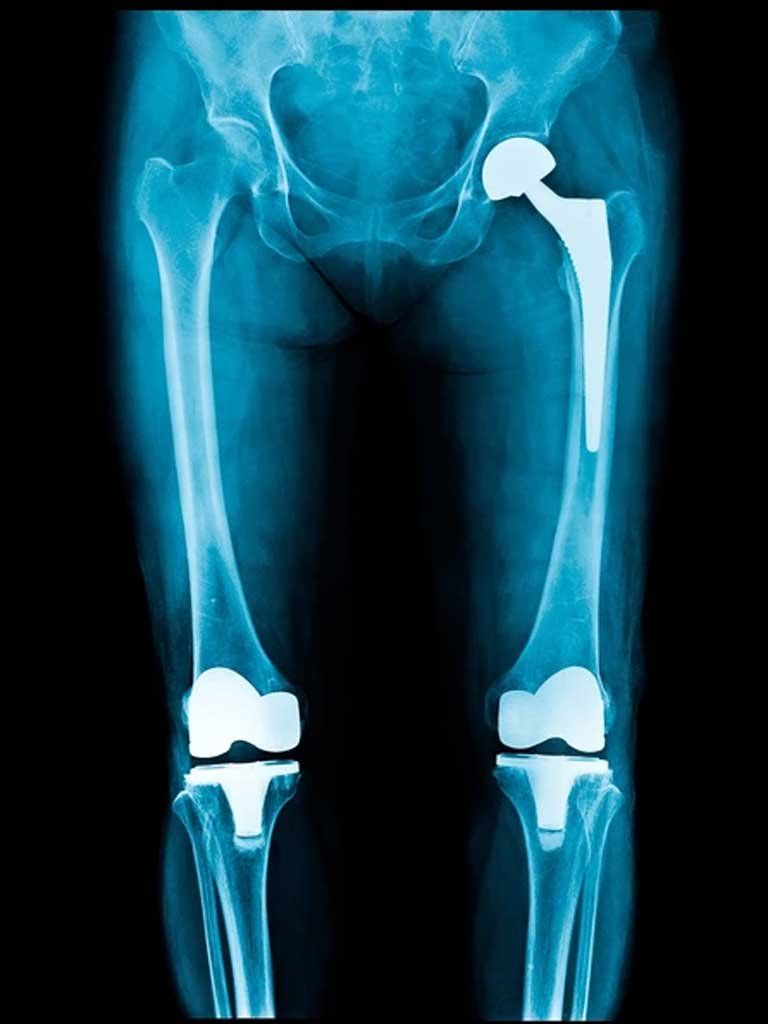

Hip pain and stiffness can severely affect mobility and quality of life. At Revive Ortho Spine Centre, our Hip Replacement Surgery service is designed to restore movement, reduce pain, and help patients regain independence. Using advanced surgical techniques and state-of-the-art implants, we deliver safe, effective, and lasting solutions for hip joint conditions.

Use of advanced implants designed for durability and natural movement